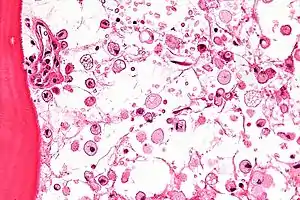

| عکاسی ریزنگاری of Gaucher disease, with cells that have the characteristic crumpled tissue paper-like سیتوپلاسم. H&E stain. | |